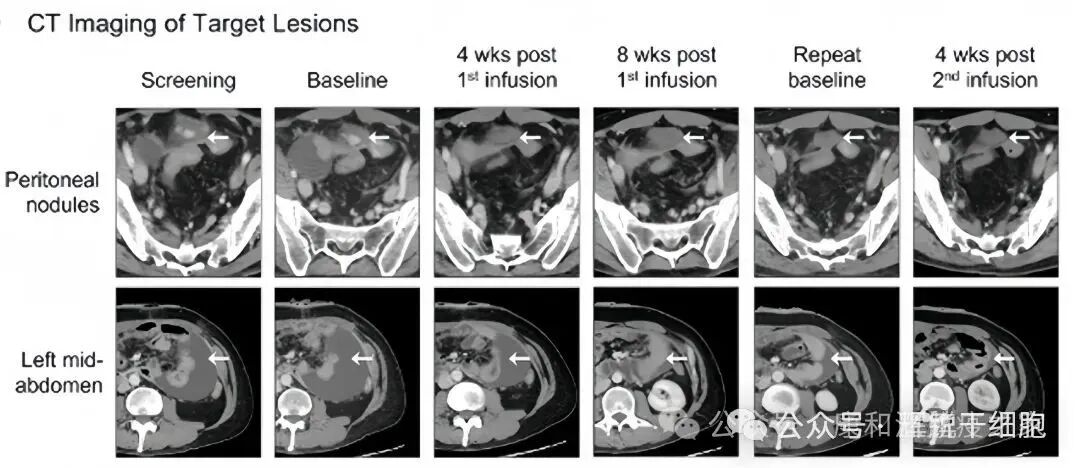

一位30多岁的患者,2019年12月确诊患有转移性胃癌,转移位置包括沿膀胱圆顶和腹膜壁的两个腹膜结节。非靶向病变包括胃壁增厚和腹水。2021年患者参加免疫细胞临床试验。输注免疫细胞后,肿瘤相关ctDNA迅速减少,基线时发现的两个腹膜靶病变明显减少,在患者腹胀改善的同时,观察到左中腹部室性腹水减少。输注免疫细胞第四周,患者达到部分缓解(PR),目标病变消失。患者的精力得到改善,胆汁性呕吐明显减少。

第 12 周进行第二次免疫细胞输注,在第二次免疫细胞输注后 4 周,患者达到完全缓解(CR),非靶向脾周结节和胃壁增厚完全消退,患者生活质量得到明显改善。